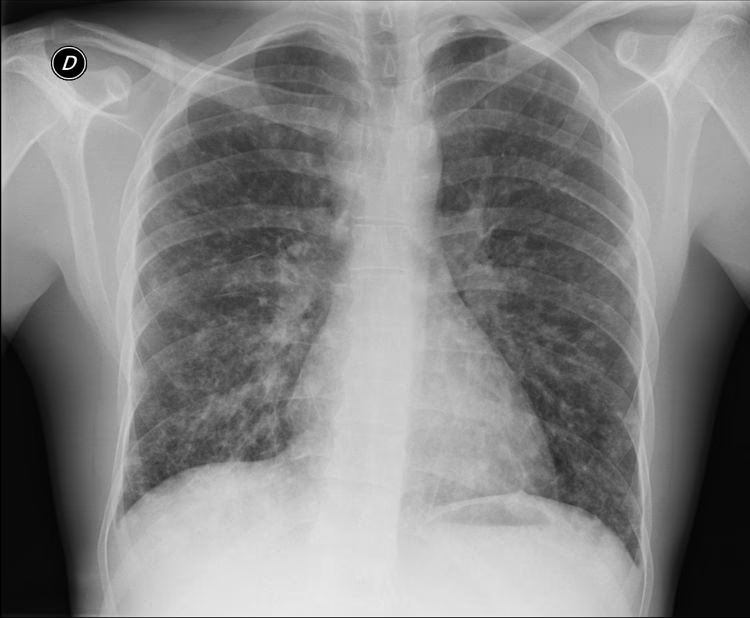

- Røntgenbillede af brystkassen: Dette er en afgørende undersøgelse, der kan visualisere infektionen. Lægen vil kigge efter hvide pletter (infiltrater) på billederne, og deres tilstedeværelse i begge lunger bekræfter diagnosen bilateral lungebetændelse.